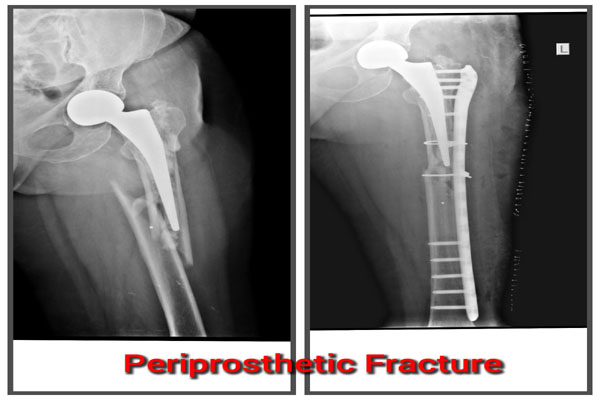

Fracture of bones is commonly handled by almost all orthopaedic surgeons in India. But dealing with comminuted intra-articular fractures (involving joints) is a night mare for most of them. It requires special expertise and experience to deal with such kind fractures. It can involve pelvic acetabular fracture, upper portion of thigh bone ( hip), lower portion of thigh bone ( femur), upper portion of arm bone (humerus head), lower portion of arm bone (humerus), lower portion of forarm bone (lower end of radius) fracture of heel bone, etc. The idea is to maintain the joint (articular) integrity and prevent the permanent loss of movements at that joint. It requires image intensifier (c-arm) to do these surgeries. May be artificial bone or autograft (patient’s own bone taken from iliac bone) to fill in the bone defect/ loss if present. The fracture may take 2- 3 months to heal. Patient may require prolonged physiotherapy to gain near normal range of motion exercises.